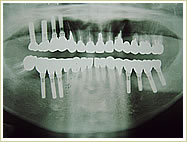

症例 65歳 男性 インプラント埋入数:11本 画像拡大

治療前 治療後